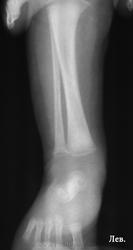

Ребенку 2-3 недели, лежит у нас по поводу остеомиелита. Дней 7 назад - появились отек, болезненность левого голеностопа, про анализы, к сожалению, ничего сказать не могу. Получил курс антибиотиков, отек спал.

В проксимальных метафизах большеберцовых - такие же полоски.

Давно не встречалась с врожденным костным сифилисом, лет 10, позабылось все (раньше, в другой больнице, видела его достаточно часто), но что могу сказать - полосы просветления в метафизах (а также полосатость ядер окостенения пяточной и таранной костей) встречаются не только при сифилисе, часто видела их у здоровых недоношенных;  при сифилисе, кроме этих полос, должно быть расширение и зазубренность зон предварительного обызвествления, симметрично в костях голеней и предплечий, клинически, обычно, не проявляется, только при третьей стадии остеохондрита, когда появляются псевдопараличи Парро - появляется припухлость, отек, ограничение движений, и это также с обеих сторон. Здесь мне видится нечеткость метафиза малоберцовой кости слева, скорее всего, обычный остеомиелит. Конечно, анализ на сифилис, все-равно, заказать надо.

К малоберцовке тоже придрался, тем более и клиника именно там была.